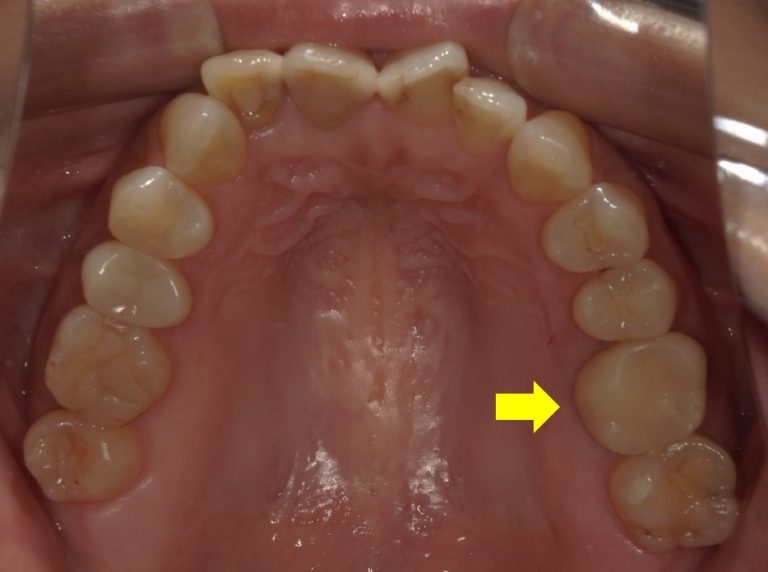

しかし、最近では保険診療でも奥歯に白い被せ物ができる流れが進んでいます。

一部条件はありますが、いわゆる4番、5番、6番の歯については白い被せ物も可能となってきました。

このように保険診療でも口腔内の条件によっては白く、きれいに治せるのです。

数年前やむなく入れた銀歯を今は保険で白くできるかもしれません。そう考えると少し希望がわきませんか?